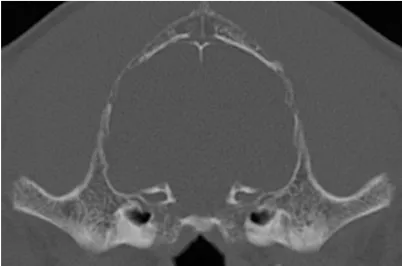

CT image dog Healthy skull

Healthy dog skull

These approaches are under-developed for veterinary patients. Consequently, we have developed a Computed Tomography based approach that allows us to screen dogs for low bone density and have a developed a novel osteodensitometry to objective quantify the density of bones. The bottom figure is a CT image of a dog skull showing that the skull is very thin when compared to a healthy skull on the top.